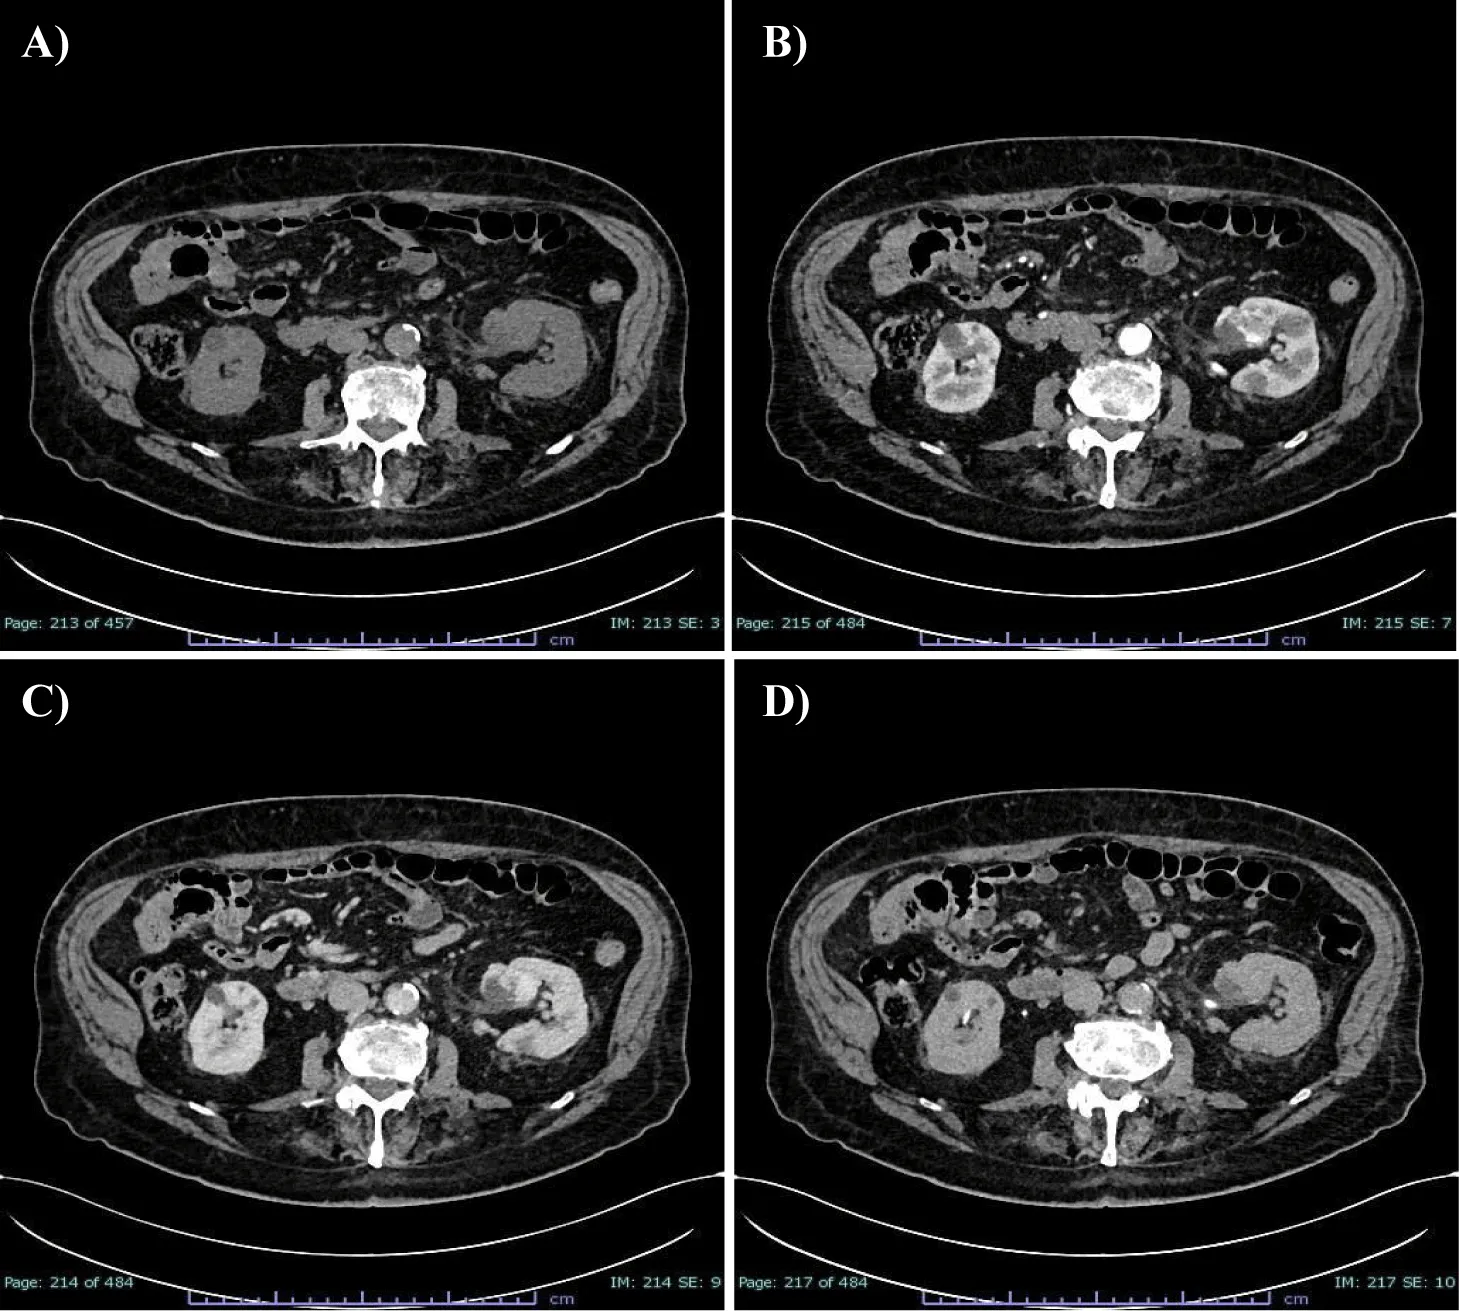

Following this finding, he underwent CT investigation without and with intravenous CM (Figure1). An axial CT scan showed an expansive formation with oval morphology in the left renal sinus outlining the organ with dimensions of about 32 x 30 mm, which tended to grow in the connective tissue of the renal sinus, slightly dislocating the inferior calyx group. In non-enhanced acquisition (Figure 1A) this formation presented a heterogeneous appearance with average values of HU of 19-20 HU, with negative values with adipose significance in some places, and peripheral areas values of 37-60 HU. In the arterial phase scans (Figure 1B), the periphery of the lesion showed a clearly annular and pseudonodular enhancement with a tendency to centripetal filling and densitometric values reaching 230 HU, thus demonstrating a highly representation of vascular tissue component. In the venous phase (Figure 1C), the lesion showed a tendency to homogeneous filling with average values up to 130 HU. The lesion showed homogeneously persistent enhancement in late scans (Figure 1D) with HU values between 50 and 70. Neither calico-pyelic dilatation was evident nor significant lymphadenopathy in the mesenteric, para-aortic and retroperitoneal stations.

This case-report is an unusual case: the patient was not symptomatic, and he incidentally discovered the kidney lesion during a routine abdomen US. Once admitted to our hospital to characterize the lesion before treatment decision, the TC and RMI imaging obtained showed features with a tendency towards heterogeneity: both methods lean towards a pre-operative diagnosis of malignant lesions. At the CT scan without CM, an inhomogeneous hypointense lesion is evident in the left renal pelvis, at the level of the lower third, which shows uneven density in all its points, varying from punctiform areas with adipose-like densitometric coefficients (from -10 HU to -2 HU), to more frankly solid areas (49-20 HU) and to sections suggesting the presence of vascular components (37-60 HU). These findings are confirmed in subsequent scans enhanced with CM and, in particular, the lesion shows a frank enhancement in the more caudal peripheral portion in the arterial phase (up to 230 HU). In the subsequent portal phase a more homogeneous contrastographic filling of the entire lesion, with values of around 130 HU, was noted confirming the presence of an important hypervascular tissue component. However, the lesion shows no frank signs of invasiveness or compression of the surrounding structures, in the absence of dilation upstream and downstream of the lesion. Furthermore, there are no signs of necrosis or calcifications within the lesion.